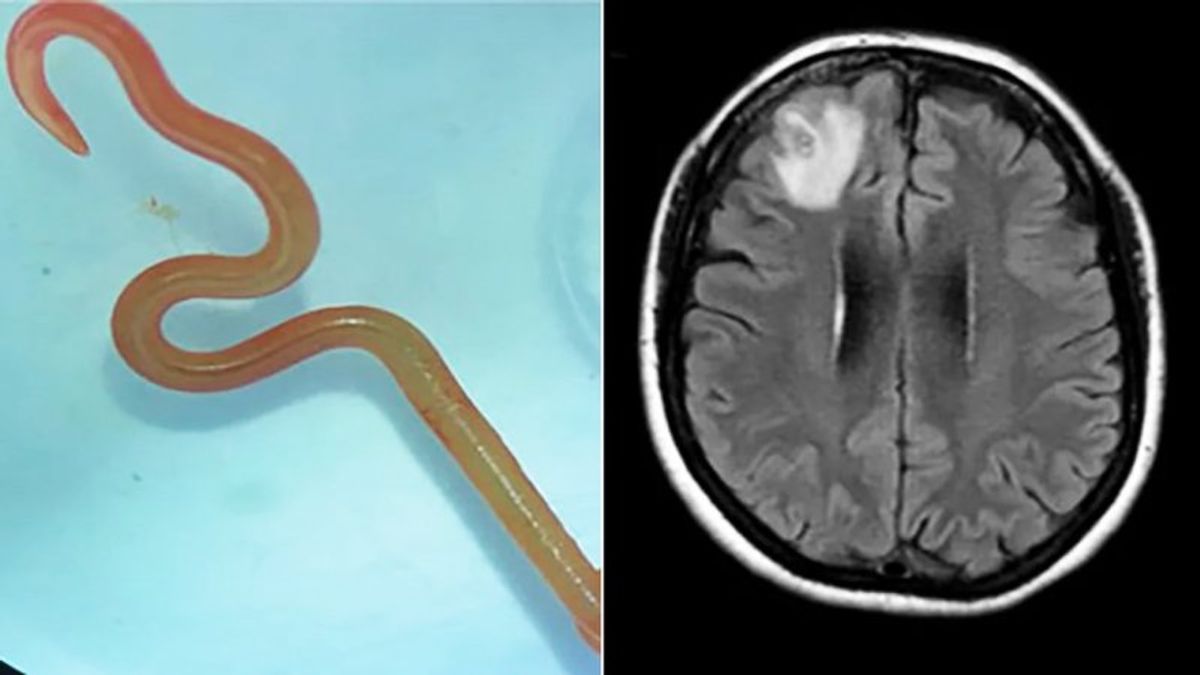

اخیرا پزشکان کرمی زنده با طول ۱۸ سانتیمتر ار مغز مردی خارج کرده و او را از مرگ نجات دادند.